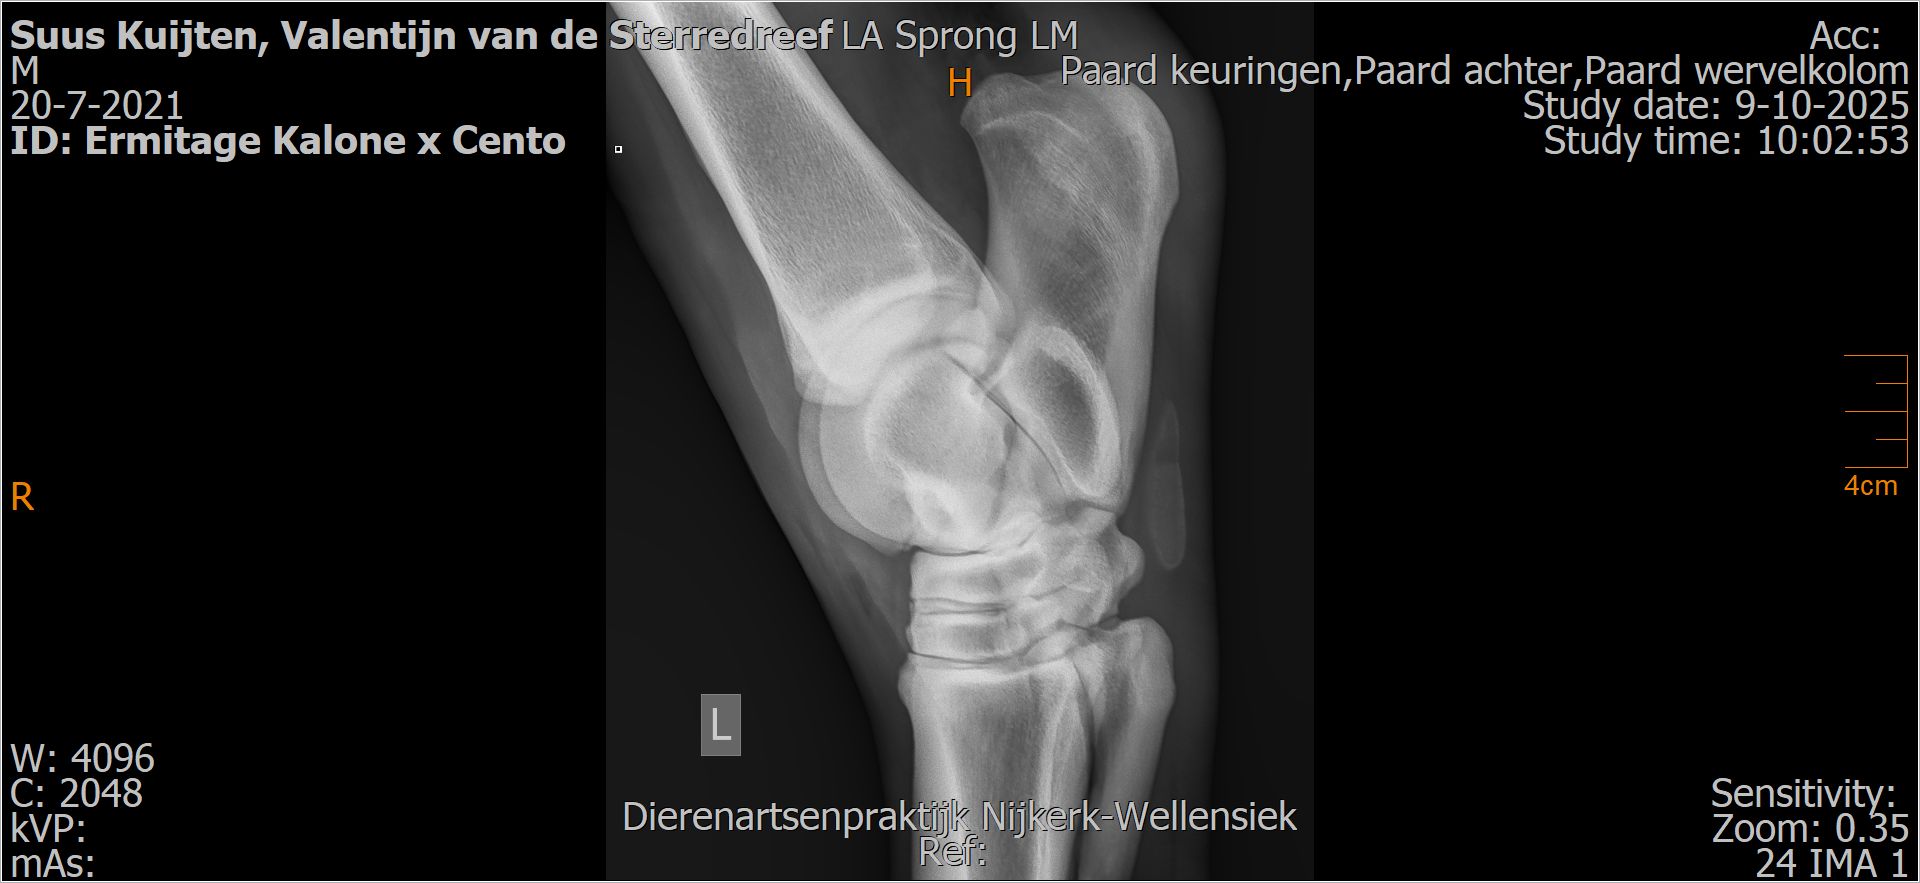

Valentijn van de Sterredreef

Leeftijd:

4

Röntgenfoto’s